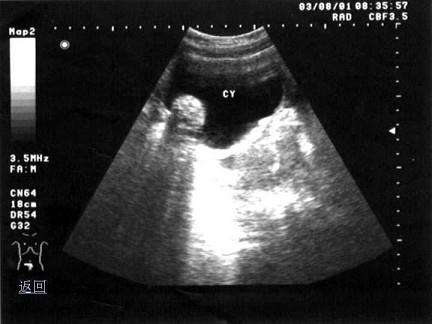

问题 女性,20岁,因月经不规则就诊。超声检查如图,最可能的诊断为?(?)

选项 A.黄素囊肿 B.黄体囊肿 C.畸胎瘤 D.附件炎性包块 E.卵巢癌

答案 C